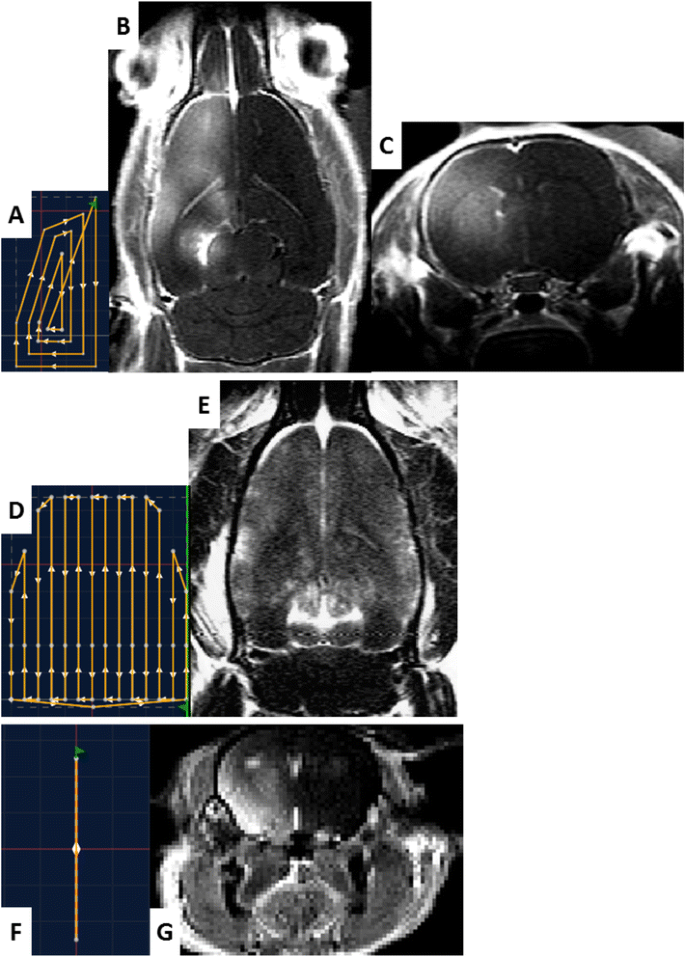

In protocol #2, several mechanical trajectories were designed to demonstrate the feasibility of BBB permeabilization along arbitrary trajectories. On rats #2.1, #2.2, and #2.3, trajectories with “A,” “X,” and “E” shapes were defined (Fig. 5). On rat #2.4, a trajectory covering the whole left hemisphere was defined (Fig. 6a). For all tested trajectories, continuous sonications were performed. They were repeated 60 times with a 100-ms pause between each execution and a moving speed of 10 mm/s. Experiments were conducted with transducer A. Finally, a trajectory covering the whole brain was designed on rat #2.5 (Fig. 6d). The acoustic pressure was kept constant to 0.6 MPa in situ along the trajectory by adapting the transmitted power thanks to a map of the rat skull transmission factor (data not shown). Transducer B was used for this protocol.

Trajectory drawing and application to hemispheric and global permeabilization. a (resp. d and f) Trajectories which were designed in the control software for hemispheric BBB disruption in rats (resp. global BBB permeabilization in rats and hemispheric BBB disruption in mice). c (resp. g) Axial T1-weighted image obtained after Gd chelate injection, showing contrast enhancement only in the hemisphere which has been disrupted in rat (resp. mice). b The corresponding T1-weighted image obtained in the same rat in horizontal orientation. e T1-weighted image obtained in horizontal orientation for the rat with global BBB permeabilization

The feasibility of hemispheric BBB permeabilization was also investigated on a C57Bl6 mouse, using the same preparation process and MRI sequences for rats. The sonication pattern was 3-ms sonications every 100 ms, and the transducer was continuously moved along a line over a whole hemisphere during 10 min (Fig. 6f). Dotarem® was then injected to visualize the disruption.

The images obtained after BBB permeabilization and Dotarem® injection are shown in Figs. 5 and 6. On T1w images, Dotarem® reaching brain tissues where the BBB has been disrupted are revealed by the contrast enhancement due to T1 shortening of surrounded water molecules. In Fig. 6, a contrast enhancement can be observed 30 min after Dotarem® injection in the whole targeted hemisphere of both rats and mice, while no specific contrast variation is detected in the non-sonicated hemisphere. One can notice that the contrast enhancement in sonicated hemisphere is not perfectly homogenous (Fig. 6b), in particular close to the left ventricle. The designed trajectory (Fig. 6a) could explain this difference, as the segments near the center of the trajectory (corresponding to the position of the ventricle) are more spaced. In the global BBB permeabilization experiment, a homogenous contrast enhancement can be seen on the whole brain, while no specific Gd penetration can be seen in the cerebellum which has not been sonicated (Fig. 6d). Figure 5 also confirms a specific contrast enhancement along the expected BBB permeabilization location only. On post-sonication T2w images, no radiological evidence of brain damages was detected.